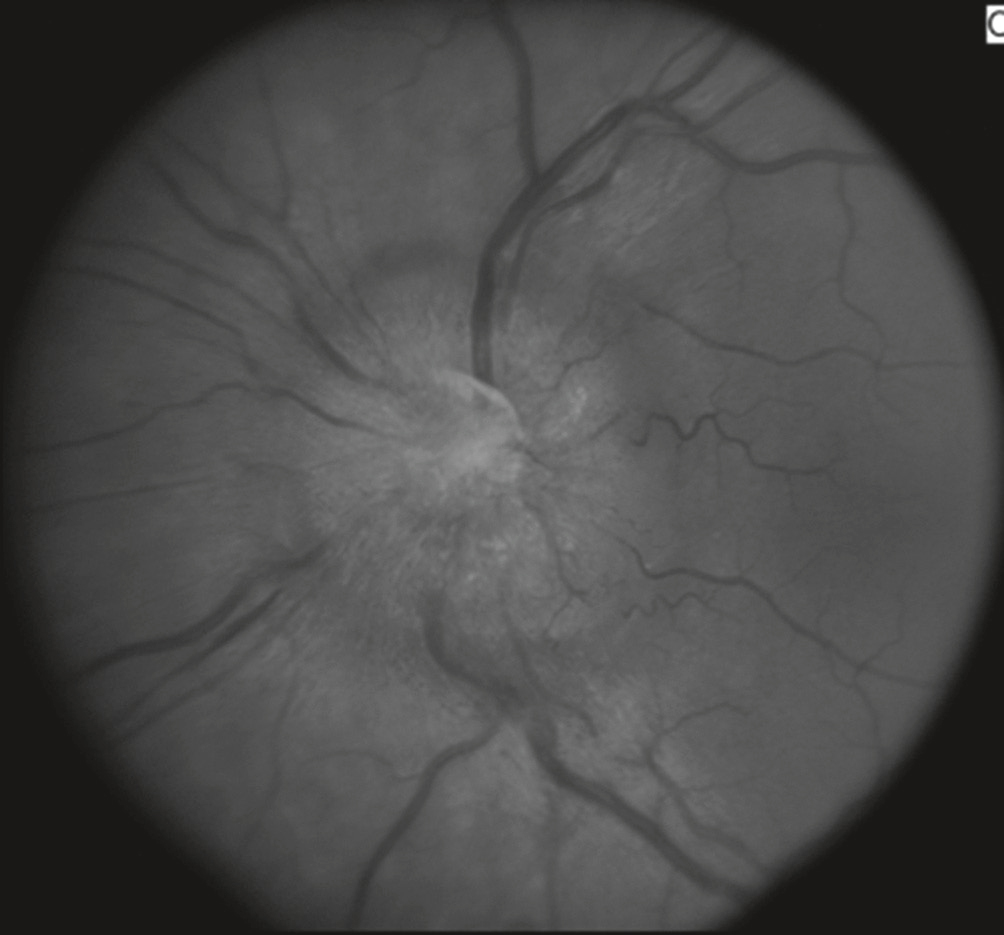

2 œdème papillaire de stase par hypertension intracrânienne (HTIC) (fig. 3.4)

œdème papillaire de stase.Cette image en niveaux de gris montre un fond d’œil avec un œdème papillaire de stase, observé à travers une photographie du nerf optique. Le disque optique apparaît flou, surélevé et ses bords sont indistincts, traduisant un gonflement anormal. Les vaisseaux rétiniens, en particulier les veines, sont dilatés et tortueux, convergeant de manière exagérée vers la papille. L’arrière-plan présente une texture granuleuse indiquant une infiltration diffuse du liquide interstitiel autour de la tête du nerf optique. L’aspect global suggère une hypertension intracrânienne aiguë ou chronique. L’irrégularité de la vascularisation péripapillaire, associée à une hyperréflectivité centrale, accentue la perte de définition du relief physiologique de la papille, ce qui est typique d’un œdème papillaire de stase sévère et potentiellement bilatéral.

- •

Clinique : -

- – éclipses visuelles à type de flou visuel uni- ou bilatéral, durant quelques secondes, survenant lors des changements de position;

- – les autres signes d’HTIC sont habituellement associés.

- • Imagerie cérébrale à réaliser en urgence.

Causes variées : tumeur cérébrale, hémorragie cérébrale ou méningée, méningite, thrombose veineuse cérébrale, formes idiopathiques d’HTIC chez la femme jeune et obèse.